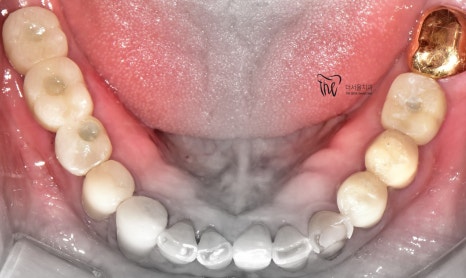

우선 교합면에서 바라보게 되면,

곳곳에 치아 결손 부위가 관찰이 되는데

이가 빠진지 시간이 꽤나 오래 되셨다는 것을

한 눈에 알아차릴 수 있습니다.

정면에서 봤을 땐, 비심미적인 모습을 보여주며

곳곳에 치경부파절증의 증세들이 드러나고

있습니다. 따라서 ,식사를 하실 때 마다

지끈거리는 통증 및 이가 시린 느낌을 지속적으로

받아오셨다 말씀을 하셨었죠.